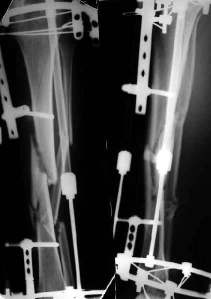

Александр Николаевич, к сожалению больной не является на контрольные осмотры. Я последний раз видел больного, когда прошло 7 месяцев после операции БОС. У него все хорошо. Каких либо жалоб и ограничений в нагрузке нет. Высылаю снимки до операции и последние снимки.